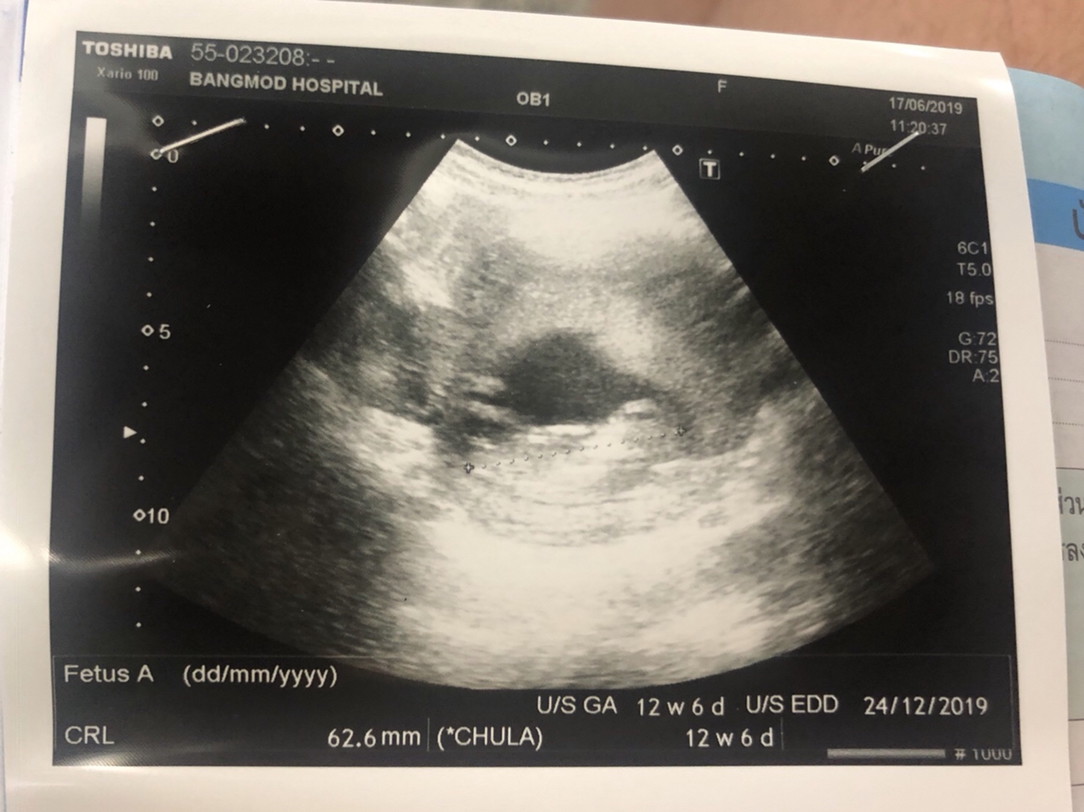

12w6d ค่าาา